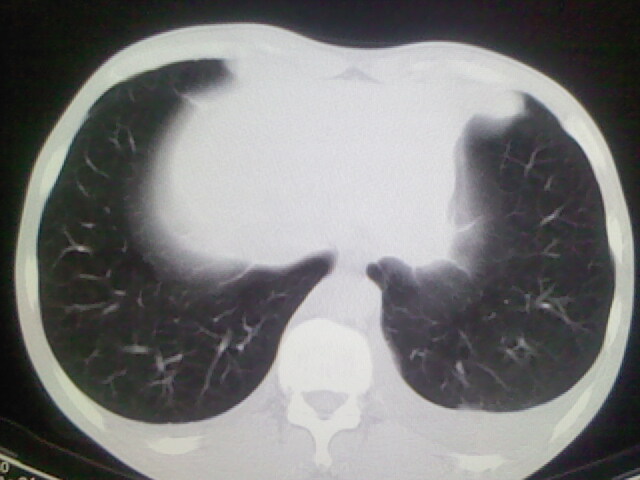

以下是引用杀毒软件在2008-9-3 6:11:00的发言:[br]侵袭性胸腺瘤------一般不侵到气管旁[br][br]考虑----纵隔淋巴瘤,心包及胸膜受累

以下是引用随光逐影在2008-9-3 7:07:00的发言:[br]1)考虑淋巴瘤可能。2)双侧胸腔积液(以左侧为甚)。3)心包积液。